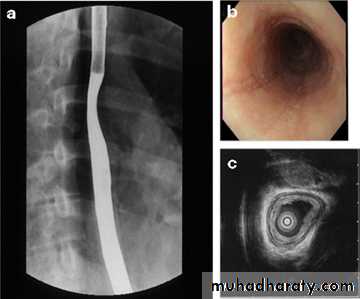

• THE OESOPHAGUSBarium Swallow:1. Conventional2. Double contrast (DC)3. Flouroscopy + spot films

Esophagus mucosa: normal thin, parallel, uniform mucosal folds 3-4 in no.in double contrast examination

esophagography is unique among esophageal studies for assessing both morphology and motility. Barium esophagography remains the study of choice for characterization of esophageal strictures. Esophageal carcinoma may demonstrate a variety of appearances on barium esophagrams.

1.Eccentric or circumferential wall thickening is greater than 5 mm.